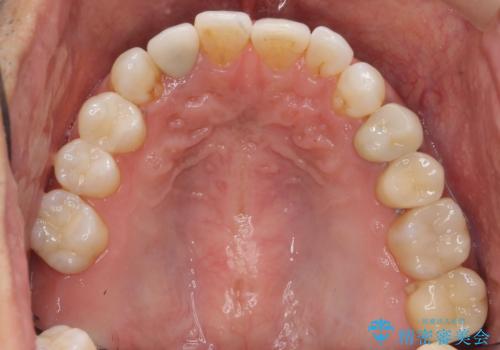

[ セラミック治療 ]目立つ奥歯の銀歯を白くする

![[ セラミック治療 ]目立つ奥歯の銀歯を白くするの症例 治療後](https://seimitsushinbi.jp/wp/wp-content/uploads/2021/11/2d1e50d0178f2ec9668274932161b9f7-500x350.jpg?v=1637229912)